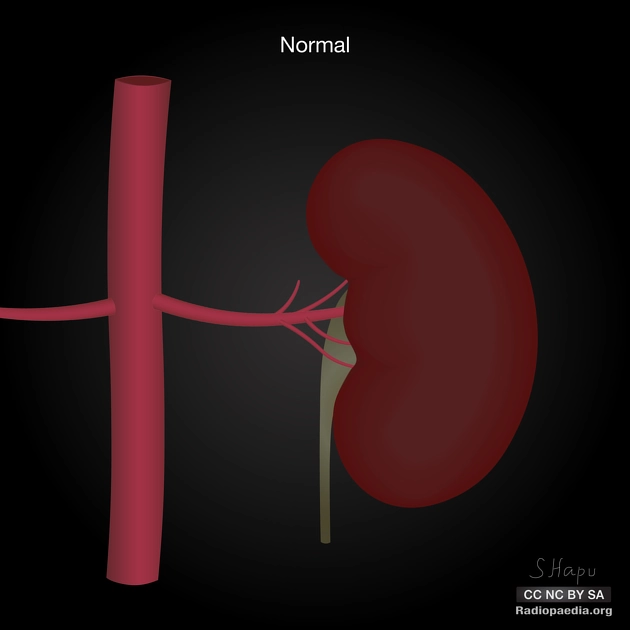

Động mạch thận phụ (Multiple renal arteries)